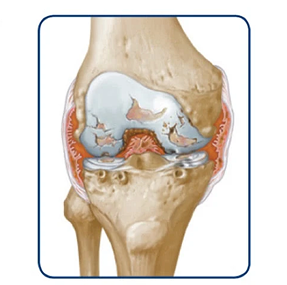

Joint bleeds—also called hemarthrosis—can happen when a joint is stressed. Repeated bleeds in the same joint may lead to chronic synovitis, where the joint lining becomes swollen and thick. Over time, this can limit movement and cause lasting joint damage.

If bleeds continue, it can degrade the cartilage and bone within the joint.

Over time, the joint may swell, change shape, and lose mobility.

Once a joint is severely damaged, it may not heal on its own. You could lose range of motion or develop a fixed joint that no longer moves. When joint damage becomes permanent, it’s called hemophilic arthropathy. Discuss treatment options with your doctor before the joint damage becomes permanent. Treatment options may include surgery.

Over time, this can lead to wearing away of the bone

Permanent damage results in a destroyed joint